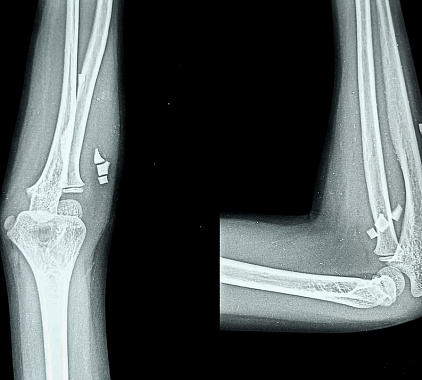

Стандарт диагностики — rg-снимок в двух проекциях: прямой (переднезадней) и боковой. Прямая показывает соотношение плечевой, локтевой и лучевой костей, ширину суставной щели, линии перелома; боковая — положение отломков, контуры локтевого отростка, «жировой» задний треугольник как признак выпота/гемартроза.

- Травма — тонкая линейная трещина, многооскольчатый перелом, смещение отломков; ступенчатость суставной поверхности головки лучевой; вывихи (чаще задние) с изменением оси предплечья; отрывные фрагменты в области прикрепления сухожилий; признаки гемартроза.